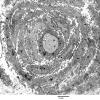

PERIPHERAL NEUROPATHY

18 HEREDITARY DISORDERS

Charcot-Marie-Tooth 1 (CMT-1) (6)